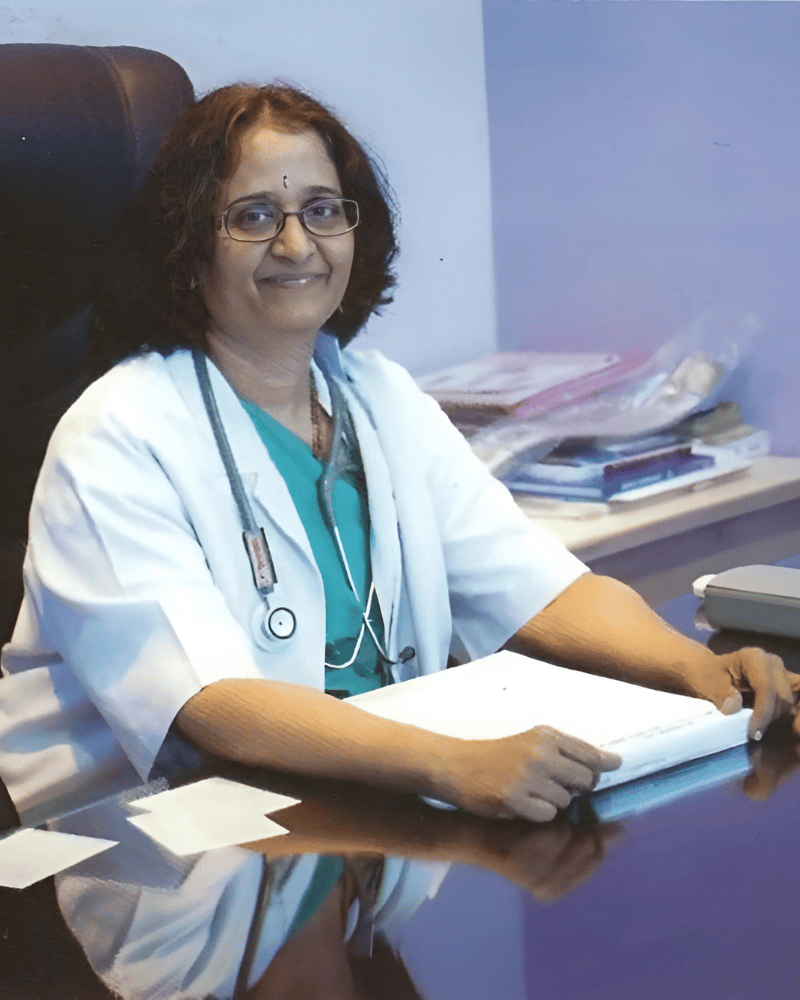

Meet Dr. G. Bhavani

Renowned IVF & Infertility Specialist

Dr. Bhavani’s four decades of hands-on practice, combined with her academic excellence and leadership roles, make her a pillar of fertility care in Hyderabad. She is especially renowned for:

- Managing both male and female infertility with precision

- Achieving strong IVF success rates through personalized protocols

- Providing ethical, patient-first care with a compassionate approach

Her reputation is backed by over 1,500+ patient stories and continuous positive reviews across platforms like Practo, Skedoc, and Vinsfertility

“Our mission is to help every couple experience the joy of parenthood through ethical, science-backed, and compassionate fertility care”

Dr. G. Bhavani, MD (Obstetrics & Gynecology)

Dr. Bhavani – A Trusted Fertility Specialist

With over four decades of hands-on experience in reproductive medicine, Dr. Bhavani has become a respected name in the field of fertility and IVF. Her patient-first approach, compassionate care, and proven expertise have helped countless couples fulfill their dream of parenthood.

From infertility evaluation to advanced treatments like IUI, IVF, and ICSI, Dr. Bhavani offers personalized fertility solutions with clinical precision and emotional support.